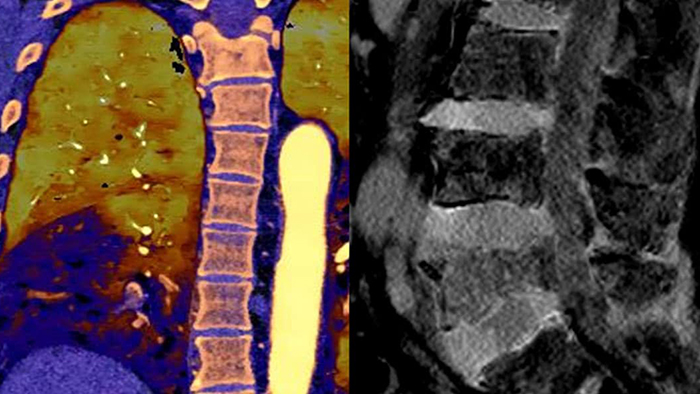

Unlike traditional CT images, spectral-detector CT images capture spectral information 100% of the time —without special planning or set-up. That means you can analyze the spectral data in any image retrospectively, using a variety of spectral viewing tools. You can, for example, adjust the monoenergetic level or get Zeffective maps.

Can you see the difference?

Move the slider to reveal spectral results when compared to conventional CT.

Conventional CT Spectral result